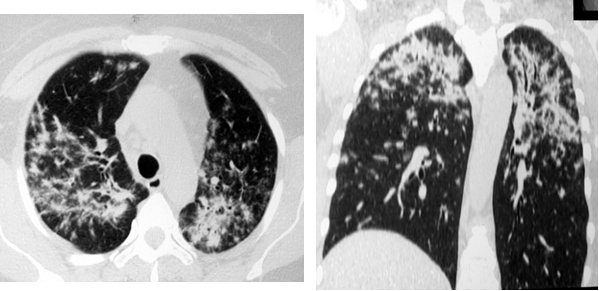

Еще одним относительно частым (20-30%) проявлением легочного саркоидоза являлся симптом локальной тени, в виде ограниченных фокусов консолидации. Как правило, изменения носили двусторонний характер с локализацией в средних и верхних легочных зонах. Контуры очагов имели преимущественно нечеткие неровные контуры, за счет инфильтрации вокруг. Нередко фокусы консолидации содержали включения воздуха. Очаги консолидации при саркоидозе отражают слияние множества мелких узелков (рис. 4, 5).

Рис. 4. РК-томограммы пациентки Г., 62 лет. Визуализируются участки альвеолярной инфильтрации округлой формы с неровными, лучистыми контурами (саркоидомы), расположенные перибронхиально

Рис. 5. РК-томограммы пациентки М., 42 лет. Субплеврально и перибронхиально с обеих сторон определяются относительно крупные очаговые тени (саркоидомы)

Картина фиброзных изменений при саркоидозе может достигать различной степени выраженности (от минимальной до грубой деформации легочного рисунка) и формируется постепенно. При хронически текущем саркоидозе, в случаях его позднего выявления, фиброз нередко оказывается первым признаком по данным лучевой визуализации и симулирует силикоз или туберкулёз. При формировании фиброза при саркоидозе часто происходит смещение главных бронхов, образование буллезных «сот», главным образом на периферии, и диффузное распространение линейных теней в легочной ткани (рис. 6).

Рис. 6. РК-томограммы больной Ч., 53 лет. Распространённый пневмофиброз с элементами буллёзной эмфиземы